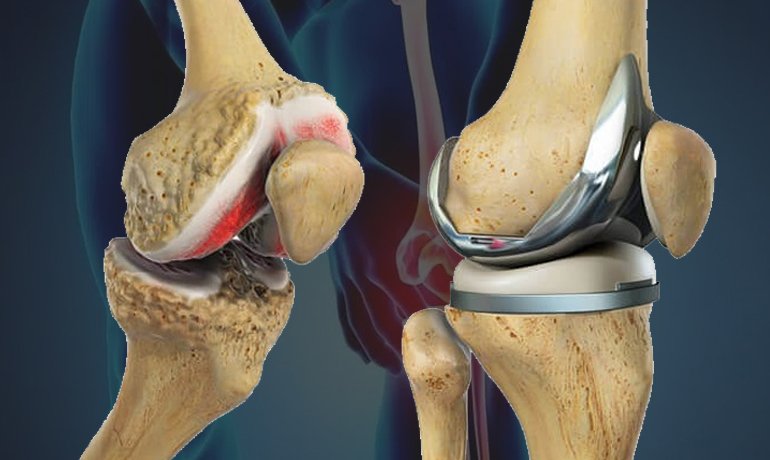

With increasing age, joints become weaker and ligaments lose their tightness, causing looseness in the knee, and in advanced cases may require knee replacement in Gorakhpur.

Conditions like osteoarthritis cause cartilage wear and joint damage, making the knee unstable.

- ACL reconstruction or ligament repair — knee surgery in Gorakhpur for severe cases